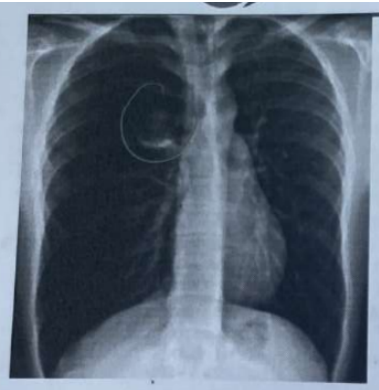

Homem, 78 anos; viúvo; aposentado; residente em área distante dos serviços de saúde; ex-tabagista (CT 44 anos maço; cessou há 20 anos/SIC); portador de hipertensão arterial, diabetes mellitus com história de febre intermitente há 4 dias sem calafrios ou sudorese, tosse produtiva com secreção espessa e amarela; taquidispneia; FR 40 irpm; uso de musculatura acessória; Sat O2 AA 89%; não teve COVID-19; pulsos artérias com pequenas amplitudes; PA 100 x 60 mmHg; FC 102 bom; oligúria; importante queda do estado geral. Chega ao pronto socorro levado por familiares; conduzido pela equipe médica assistente multidisciplinar à sala de emergência; bradpneico; nível de consciência rebaixado; expressando palavras desconexas (GSG 8). Na condução diagnóstica e terapêutica realizou a telerradiografia de tórax a seguir mostrada. Diante da alteração encontrada, a conduta mais adequada é: